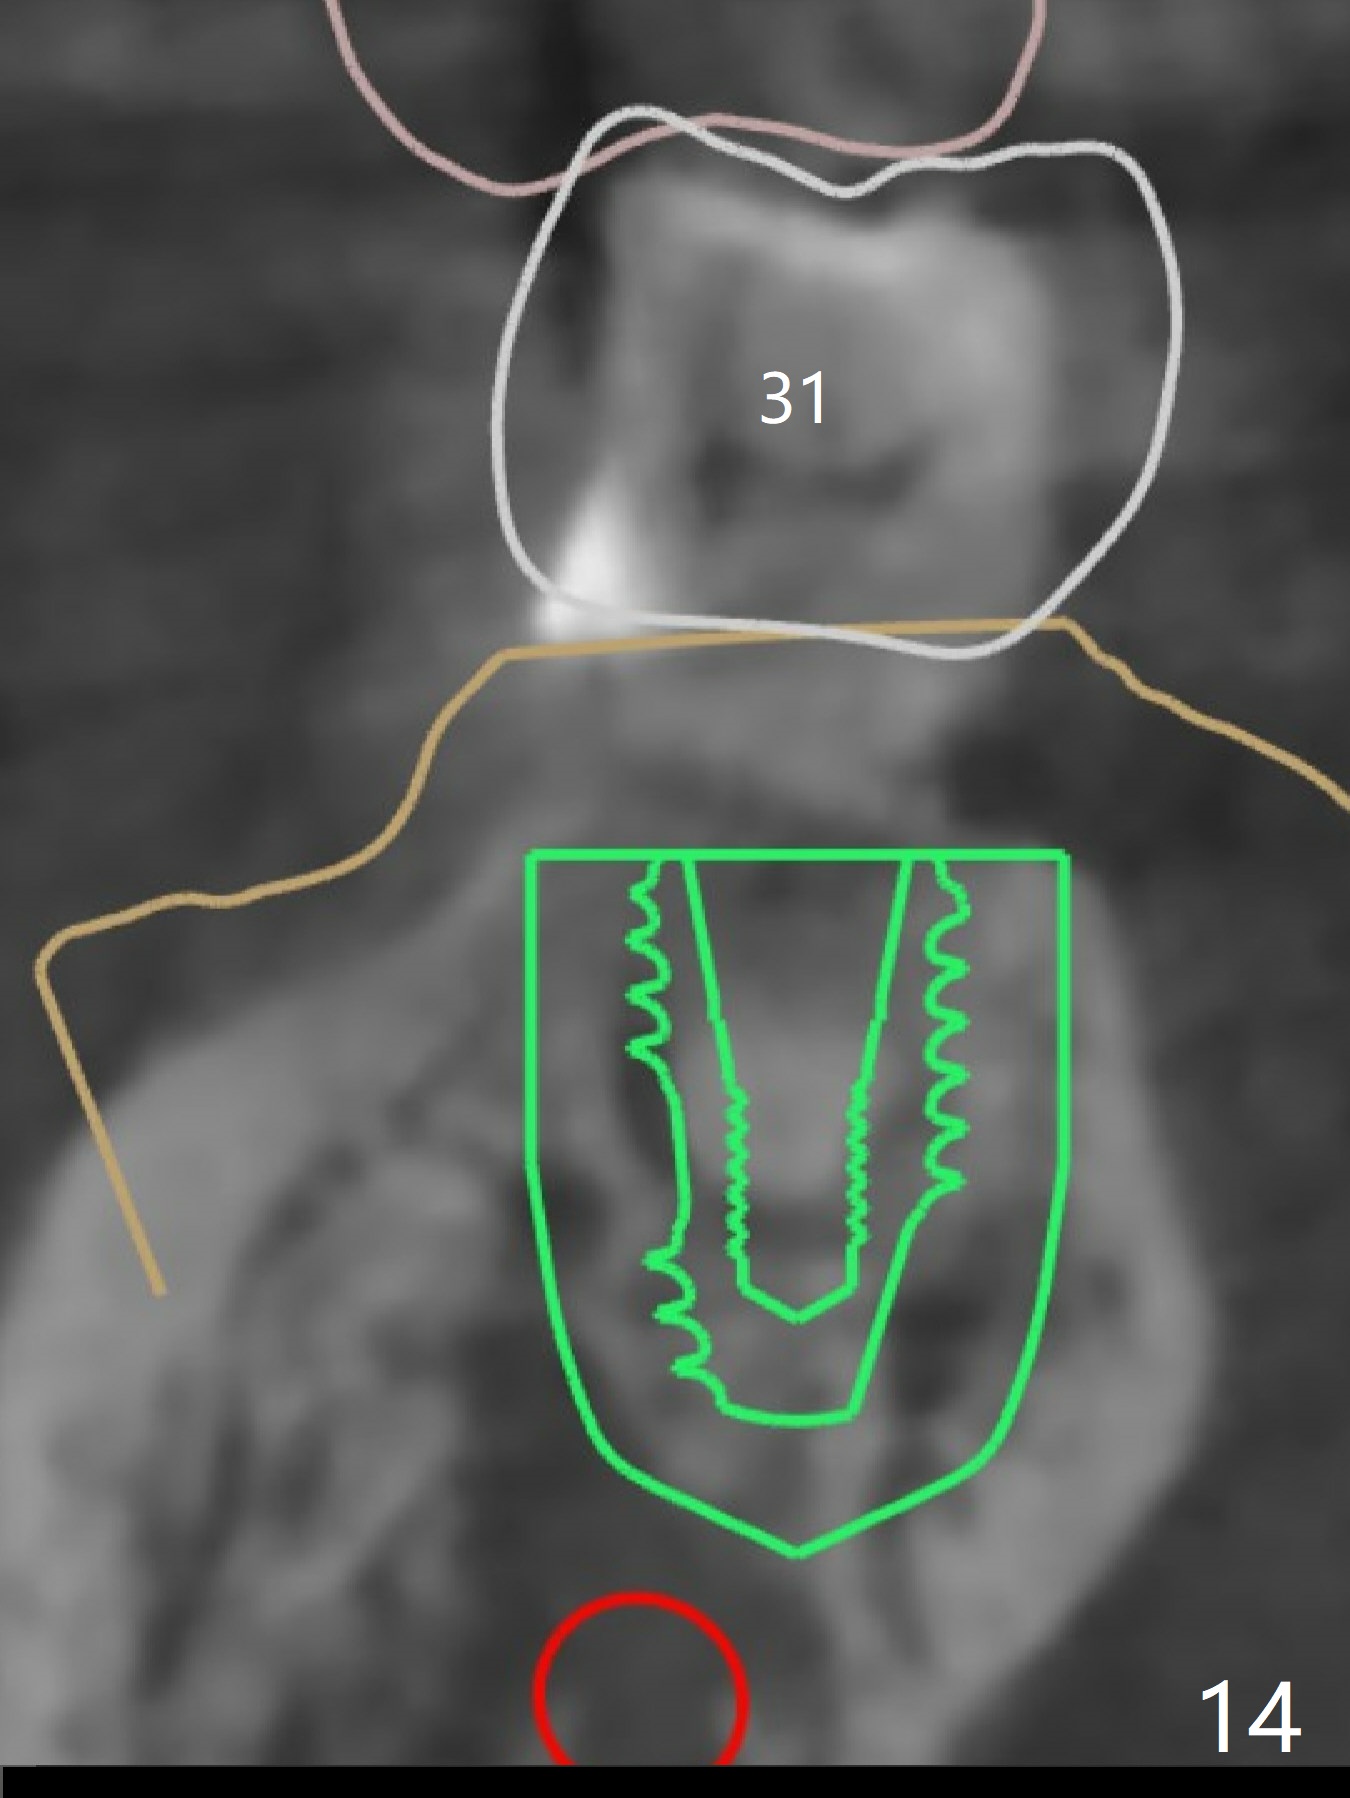

The extraction socket of #31 has a thin septum (Fig.2), which is removed partially with 12 mm bone trimmer (Fig.3). After placement of a 5x9 mm FC implant (~40 Ncm) and 6 mm bone profile drill, a 5.5x4(2) mm abutment is incompletely seated (Fig.5 <) and later is changed to a 4.5x1 mm temporary abutment (Fig.6, 8 T). The latter is used to fabricate a provisional, which in turn supports the distal papilla (Fig.8 *). The gingiva is slightly erythematous immediately post periodontal dressing removal (3 weeks postop, Fig.9). Take CT to confirm whether the cortical drill helps keep the #29 implant lingual. Use a profile drill at #29 if crestal bone loss is not obvious. There is bone coronal to #29 implant 4 months postop (Fig.10). Upon incision, the ridge is rounded (Fig.10'), but the implant appears to be buccally placed (Fig.10'' (post high speed handpiece and 5.5 mm profile drill)). The latter is confirmed by CT (Fig.12, as compared to design (Fig.11)). In spite of use of cortical drill coronally, the implant is still deviated buccally due to contrasting deferential bone density linguobuccally (Fig.13). By comparison, there is no such bone density differential involving an immediate implant at #31; the implant is placed in the socket without contacting the buccal or lingual cortices (Fig.14). The final implant is the same as expected (Fig.15). To avoid implant deviation in the lower premolar region, leave the root in place until osteotomy is finished. Five months postop, the temporary and healing abutments at #31 and 29 change to pair ones (Fig.16). Since there is limited clearance from the crestal bone, smaller abutments are used with the apparently same degree of seating (Fig.17). The abutments are prepared due to the mesial (#31) and buccal (29) tilt before impression.